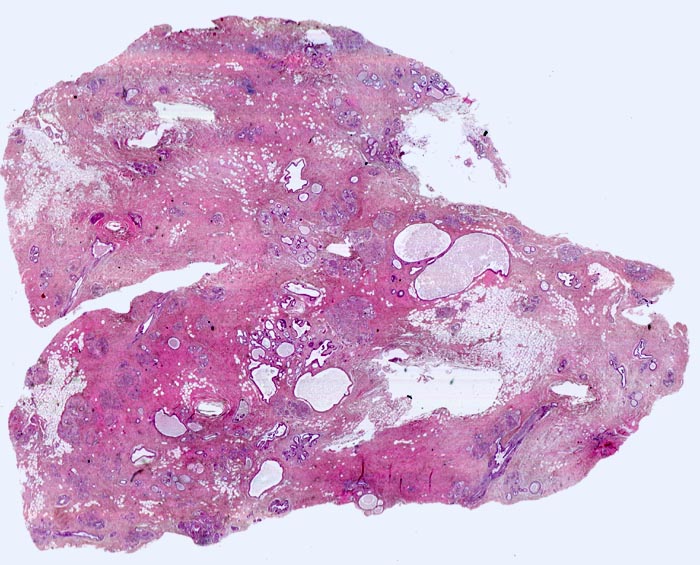

Ausgeprägte Fibrose und zystisch erweiterte Gangstrukturen in organoider Anordnung.

In der Mitte rechts einige Gänge mit gewöhnlicher intraduktaler Epithelhyperplasie ohne Atypie: Polymorphe, sich überlagernde spindelige Zellen. Fliessende Anordnung der Zellen. Schlitzförmige und irregulär geformte Lumina.

Herdförmig apokrine Metaplasie des Drüsenepithels: hochprismatische Zellen mit sehr reichlichem feingranulärem eosinophilem Zytoplasma und runden Kernen.

Rundlicher blauvioletter Mikrokalk in den Azini benigner Drüsenläppchen.

Kolumnarzellveränderung: erweiterte Drüsen ausgekleidet von hochprismatischem Epithel mit apikalen Nasen (snouts) gefüllt mit Sekret und teilweise assoziiert mit Mikrokalk.

Im Zentrum des Präparates stark erweiterte Gänge mit intraduktalen peripheren Papillomen.

Alle Drüsen zeigen eine erhaltene äussere abgeflachte Myoepithelschicht mit hellem Zytoplasma.